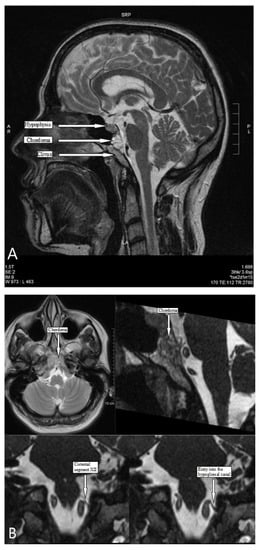

2.1. Clinical Findings and Imaging